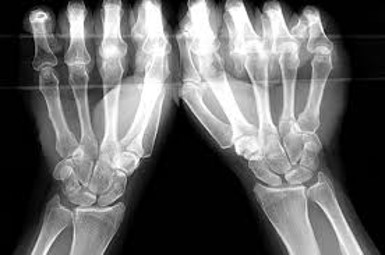

An x-ray can be beneficial to review bony alignment, and to check for any abnormalities such as widened gaps between carpal bones and dorsal or volar intercalated segment instability (DISI/VISI).

A clenched fist AP view can be used to evaluate the widening scapho-lunate gap and is performed bilaterally with both hands in a clenched fist often holding a pencil. The clenching brings the capitate proximally and emphasises any widening of the scapho-lunate interval. Additional imaging such as an MRI may also be required.

Stress AP view using clenched fist pencil grip to assess the scapho-lunate gap

Photo source: the Journal of Hand Surgery